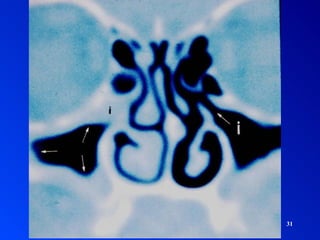

SINUSITIS Interrogatorio SintomatologíaExamen Físico Palpación – percusión Rinoscopia anterior Rinoscopia posterior Exámenes complementarios Imagenología: Rx, TAC, RM Fibroscopía - Endoscopía Punción DIAGNOSTICO

• 29.

• 30.

• 31.